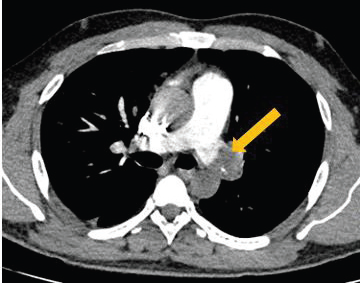

Figure 1:CT pulmonary angiography (CTPA) axial images demonstrate

a well-defined intraluminal thrombus with calcific foci causing near complete

luminal occlusion of the left main pulmonary artery, in

keeping with pulmonary embolism. The total modified Wells score is

4.5 (>4), indicating that pulmonary embolism is likely